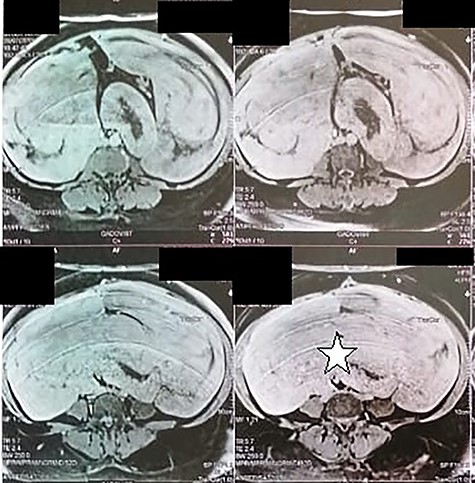

A 51-year-old woman presented to the department of surgery, with a 6 months history of an increasing pelvic heaviness and chronic constipation without urinary or gynecological disorders. Her medical history was positive for a total hysterectomy for multiple uterus fibroids, 8 years ago with no remarkable comorbidities. Upon physical examination, she had a palpable mass located in the left flank with a posterior and iliac extension. It was firm with regular borders. The patient’s blood cell counts, serum electrolyte levels, renal and liver functions, CA-125 and carcinoembryonic antigen were all within normal limits. Abdominal magnetic resonance image revealed a 32 × 29 × 12 cm retroperitoneal tissular mass with a signal that is isointense to that in muscle on T1-weighted images, and a homogeneous enhancement by contrast material (Fig. 1). The patient underwent surgical excision of the tumor. Careful exploration of the abdominal cavity revealed the retroperitoneal growth pattern of the mass extending from the pelvis to the flanks without adherences to adjacent structures. On gross, the specimen weighed 1660 g and measured 33 × 28.5 × 12 cm. It was well-circumscribed, firm, white-gray colored at sectioning. Hematoxylin–eosin-stained sections revealed mature smooth muscle cells with blunt-ended nuclei, and abundant eosinophilic cytoplasm arranging in intersected fascicles. The stroma contained vessels with mural hyalinization and myxoid changes (Fig. 2). Necrosis and nuclear atypia were absent. Mitotic count was 1/20HPF without atypical mitotic figures. On Immunohistochemistry, tumoral cells showed strong, diffuse positivity with smooth muscle actin (SMA) desmin, estrogen and progesterone receptors. They were negative for CD117, DOG1, PS100 and CD34 (Fig. 3). After surgery, the patient has had no recurrence (1 year).

Abdominal magnetic resonance showing a 32 × 29 × 12 cm retroperitoneal tissular mass with a signal that is isointense to that in muscle on T1-weighted images (white star).